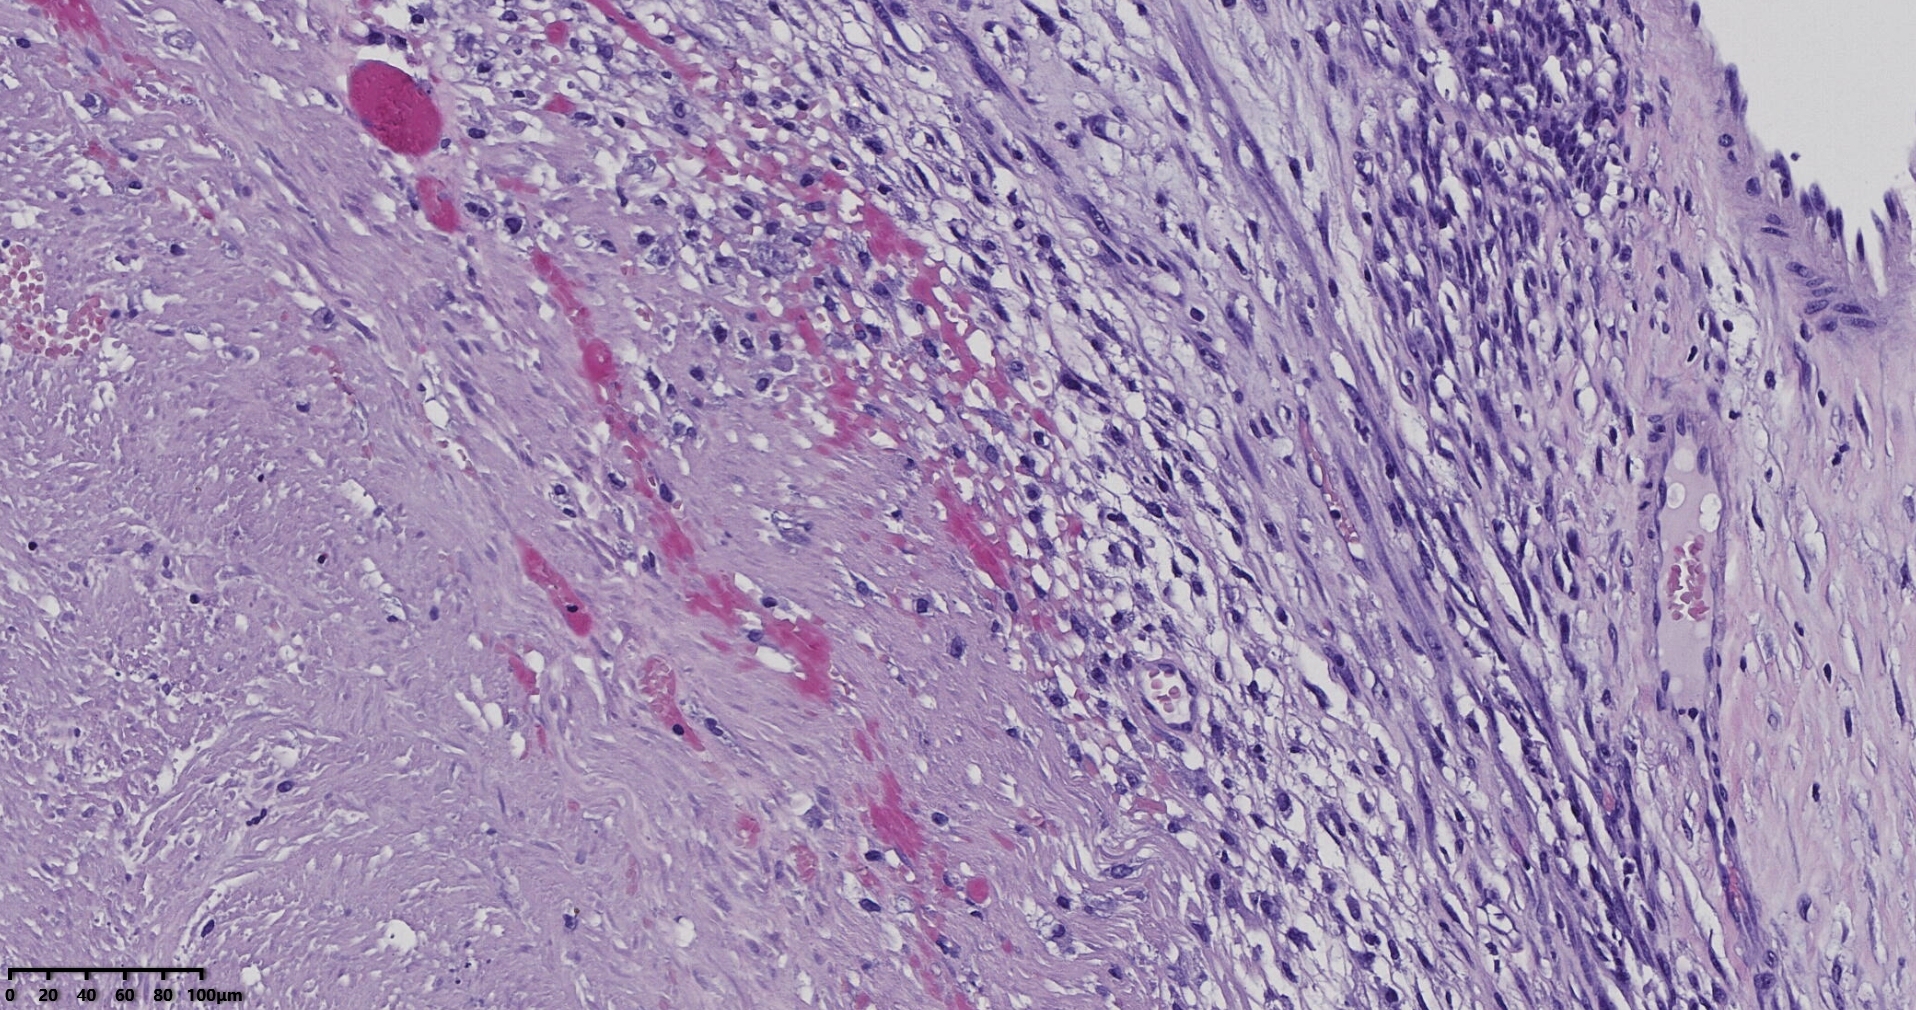

送检灰白肿物十余个,直径多在2-3厘米,切面均为灰白、实性,质地韧,其中一个大肿物,直径约7厘米,切片灰白灰红,质地韧当时取材时印象还是平滑肌瘤,伴变性,不考虑肉瘤,因为形态规整,质地韧,不脆,切面灰白,不是灰黄。

镜下所见小肿物无特殊,大肿物瘤细胞密集,中心区有变性、坏死,瘤细胞核有异型性。大肿物补充取材,发现,部分区域切面灰黄,这个区域,瘤细胞更密集,异型性更显著。肿物边缘有薄层正常平滑肌组织被覆,靠近边缘瘤细胞最密集,局部瘤组织内小血管较丰富。